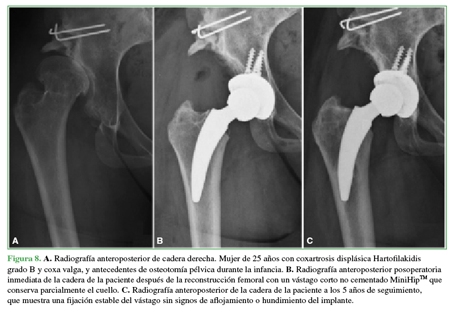

Con el objetivo de analizar los problemas técnicos encontrados al reconstruir el fémur proximal de pacientes con artrosis secundaria a displasia congénita de cadera tratados con una ATC utilizando un vástago corto, se analizó prospectivamente una serie consecutiva de 116 casos con diagnóstico de displasia de cadera tratados con tallo de conservación cervicometafisaria tipo 2B.42

La población de pacientes consistió en 11 mujeres y 6 hombres con una edad promedio de 43 años (DE ± 9.97). En cinco casos, la displasia de cadera fue bilateral; en uno caso, se realizó ATC bilateral en un tiempo y, en cuatro de estas caderas, se realizó un tratamiento quirúrgico secuencial en diferentes etapas debido a las posibles complicaciones de cirugías bilaterales complejas en un tiempo que requieren reconstrucciones sustanciales. El IMC promedio fue de 27 kg/m2 (DE ± 4,50). Cuatro casos presentaron antecedente de osteotomía pélvica durante la infancia (2 osteotomías de Salter y 2 de Chiari), mientras que cuatro casos habían sido sometidos a una osteotomía desrotadora y una osteotomía varizante de cuello femoral. El seguimiento medio fue de 41.22 meses (rango 24-61).

Todos los pacientes mostraron una mejoría estadísticamente significativa cuando se compararon los valores preoperatorios y posoperatorios del HHSm (54,19 vs. 94,57; p = 0,0001) y de escala analógica visual de dolor (8,71 vs. 0,71; p = 0,0003). No se encontraron casos de dolor de muslo, inestabilidad o infección. Se diagnosticó un caso de aflojamiento del cotilo y un caso de fractura periprotésica de fémur a los 8 meses y 45 días, respectivamente. La supervivencia global fue del 84,7% a los 5 años (IC95% 64,4-105,3) considerando revisión por cualquier motivo como falla terapéutica. Cuando se evaluó el rendimiento del vástago considerando como falla a la reoperación por aflojamiento del tallo solamente, la tasa de supervivencia fue del 100% a los 5 años (Figura 8).